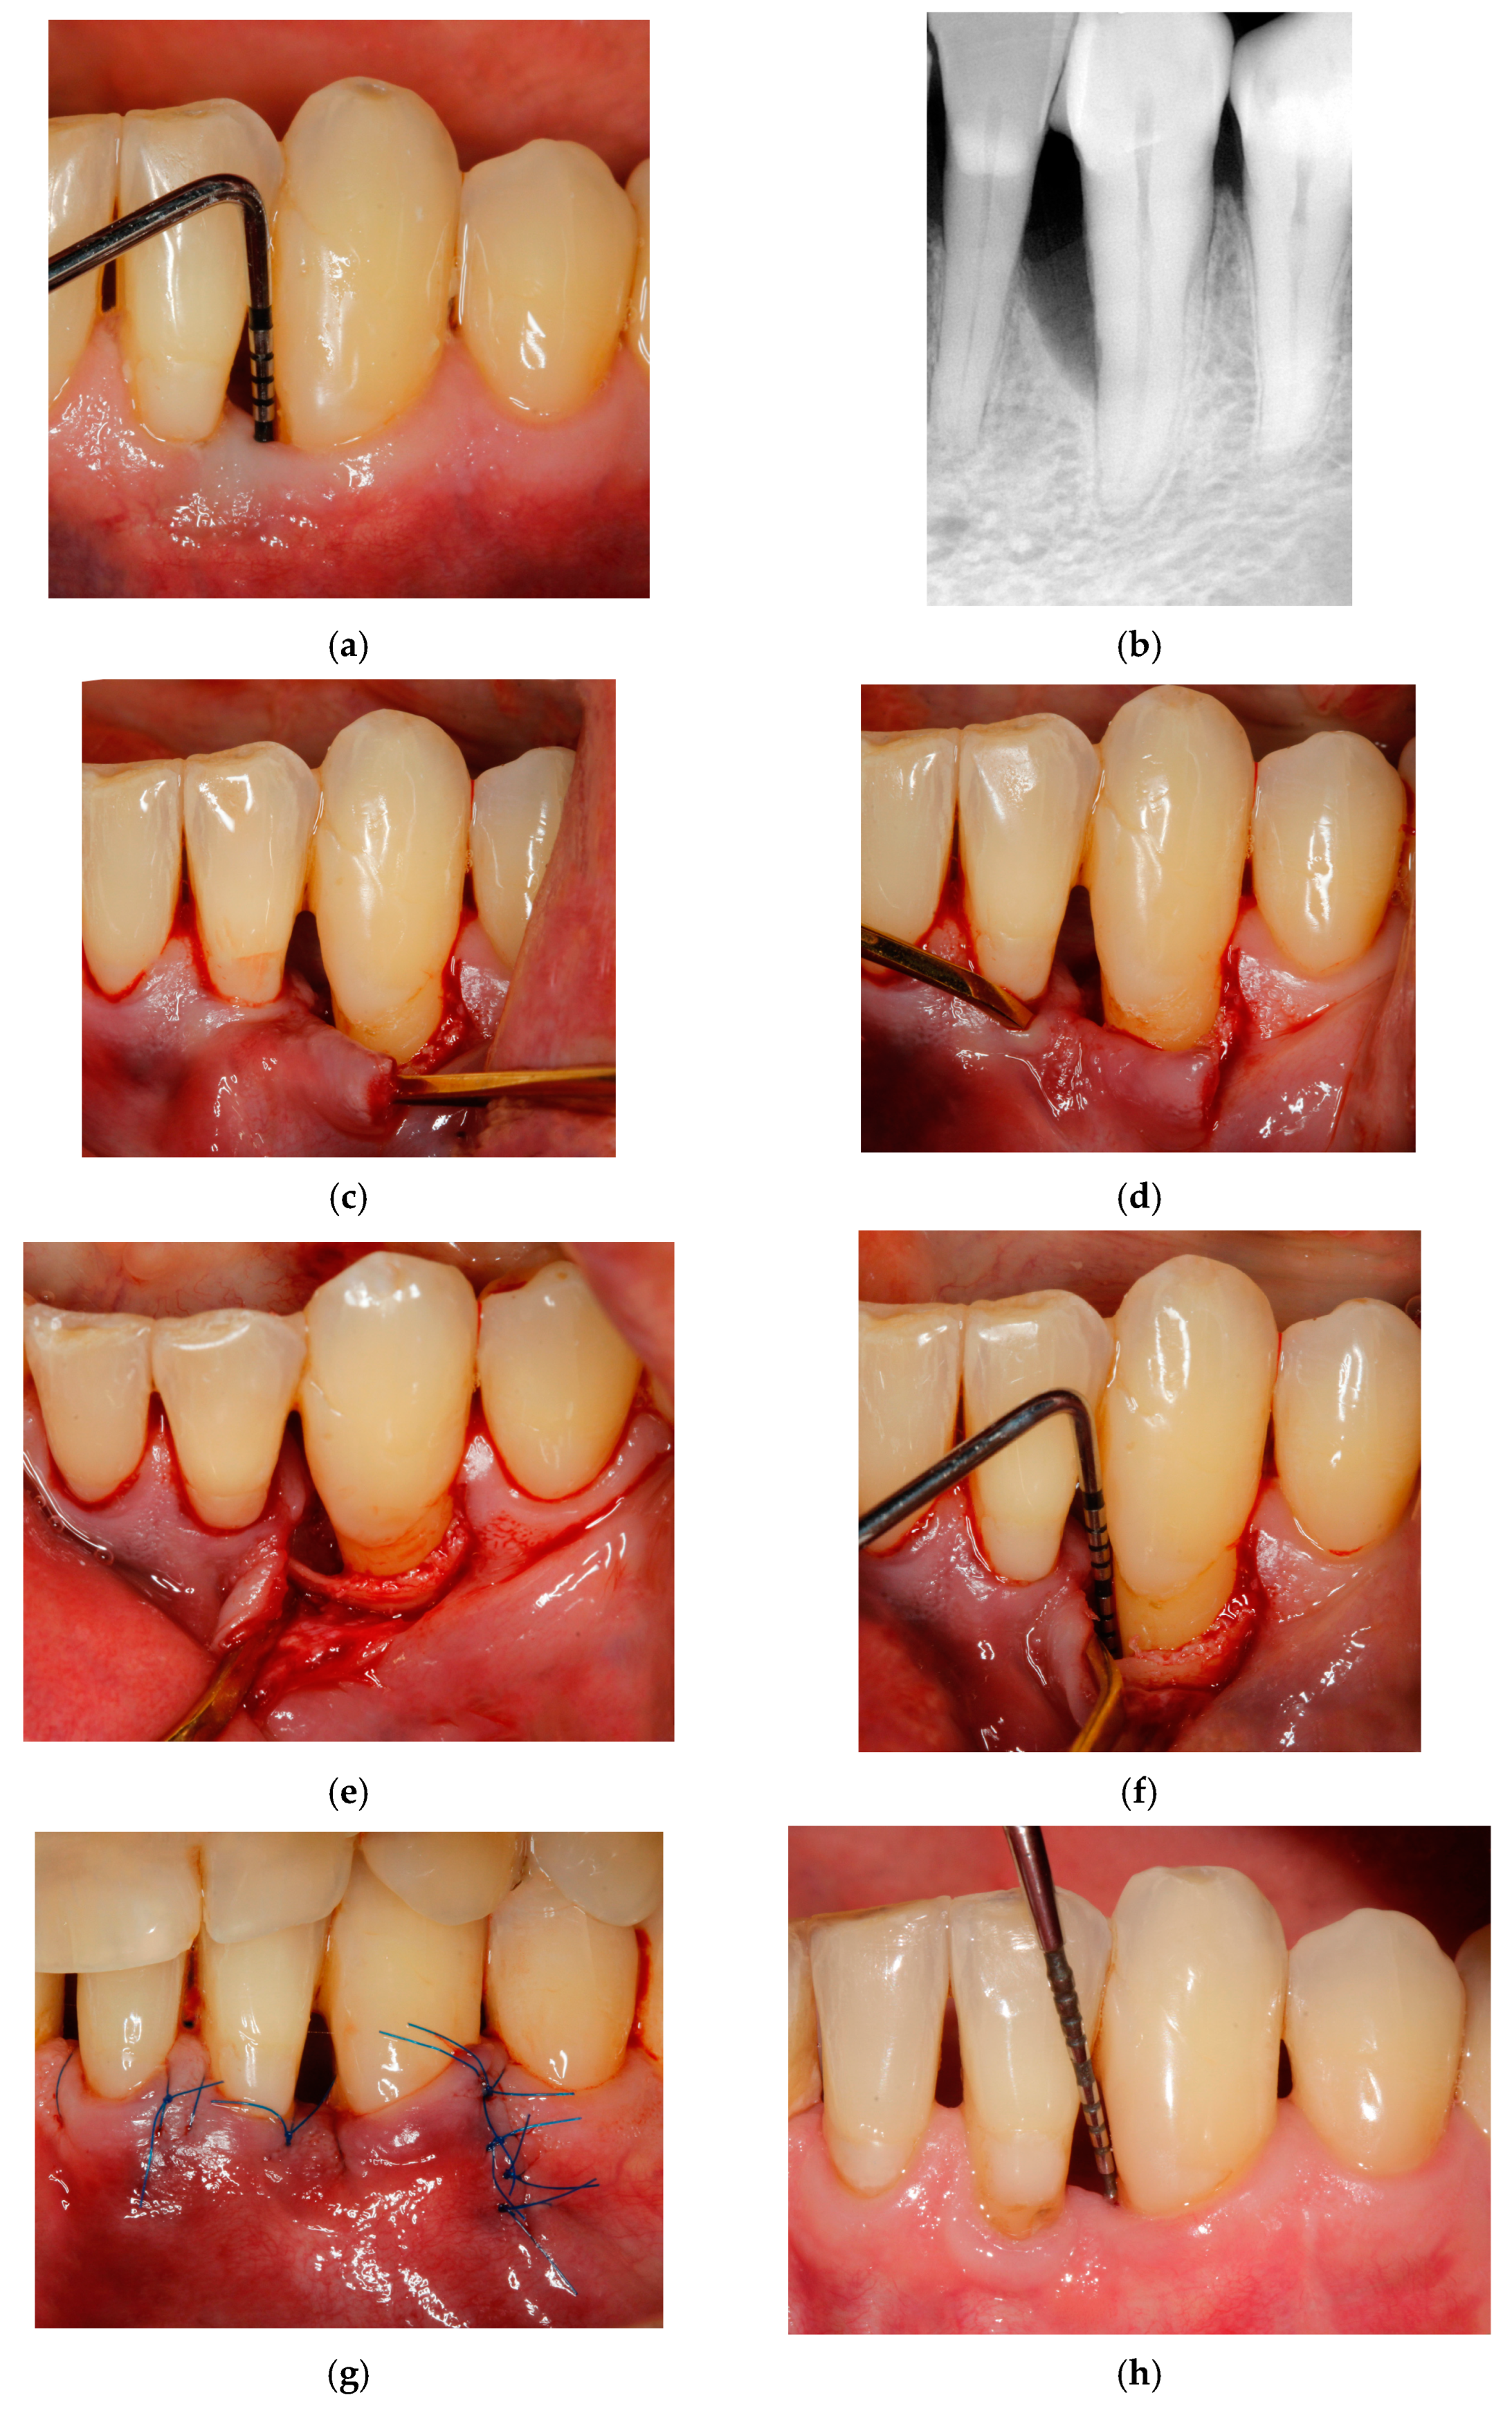

Entire Papilla Preservation Technique with Enamel Matrix Proteins and Allogenic Bone Substitutes for the Treatment of Isolated Intrabony Defects: A 3-Year Follow-Up of a Prospective Case Series

- Górski, B.; Kowalski, J.; Wyrębek, B. Entire Papilla Preservation Technique with Enamel Matrix Proteins and Allogenic Bone Substitute for the Treatment of Isolated Intrabony Defects: A Prospective Case Series. Int. J. Periodontics Restor. Dent. 2023, 43, 387–397. [Google Scholar]